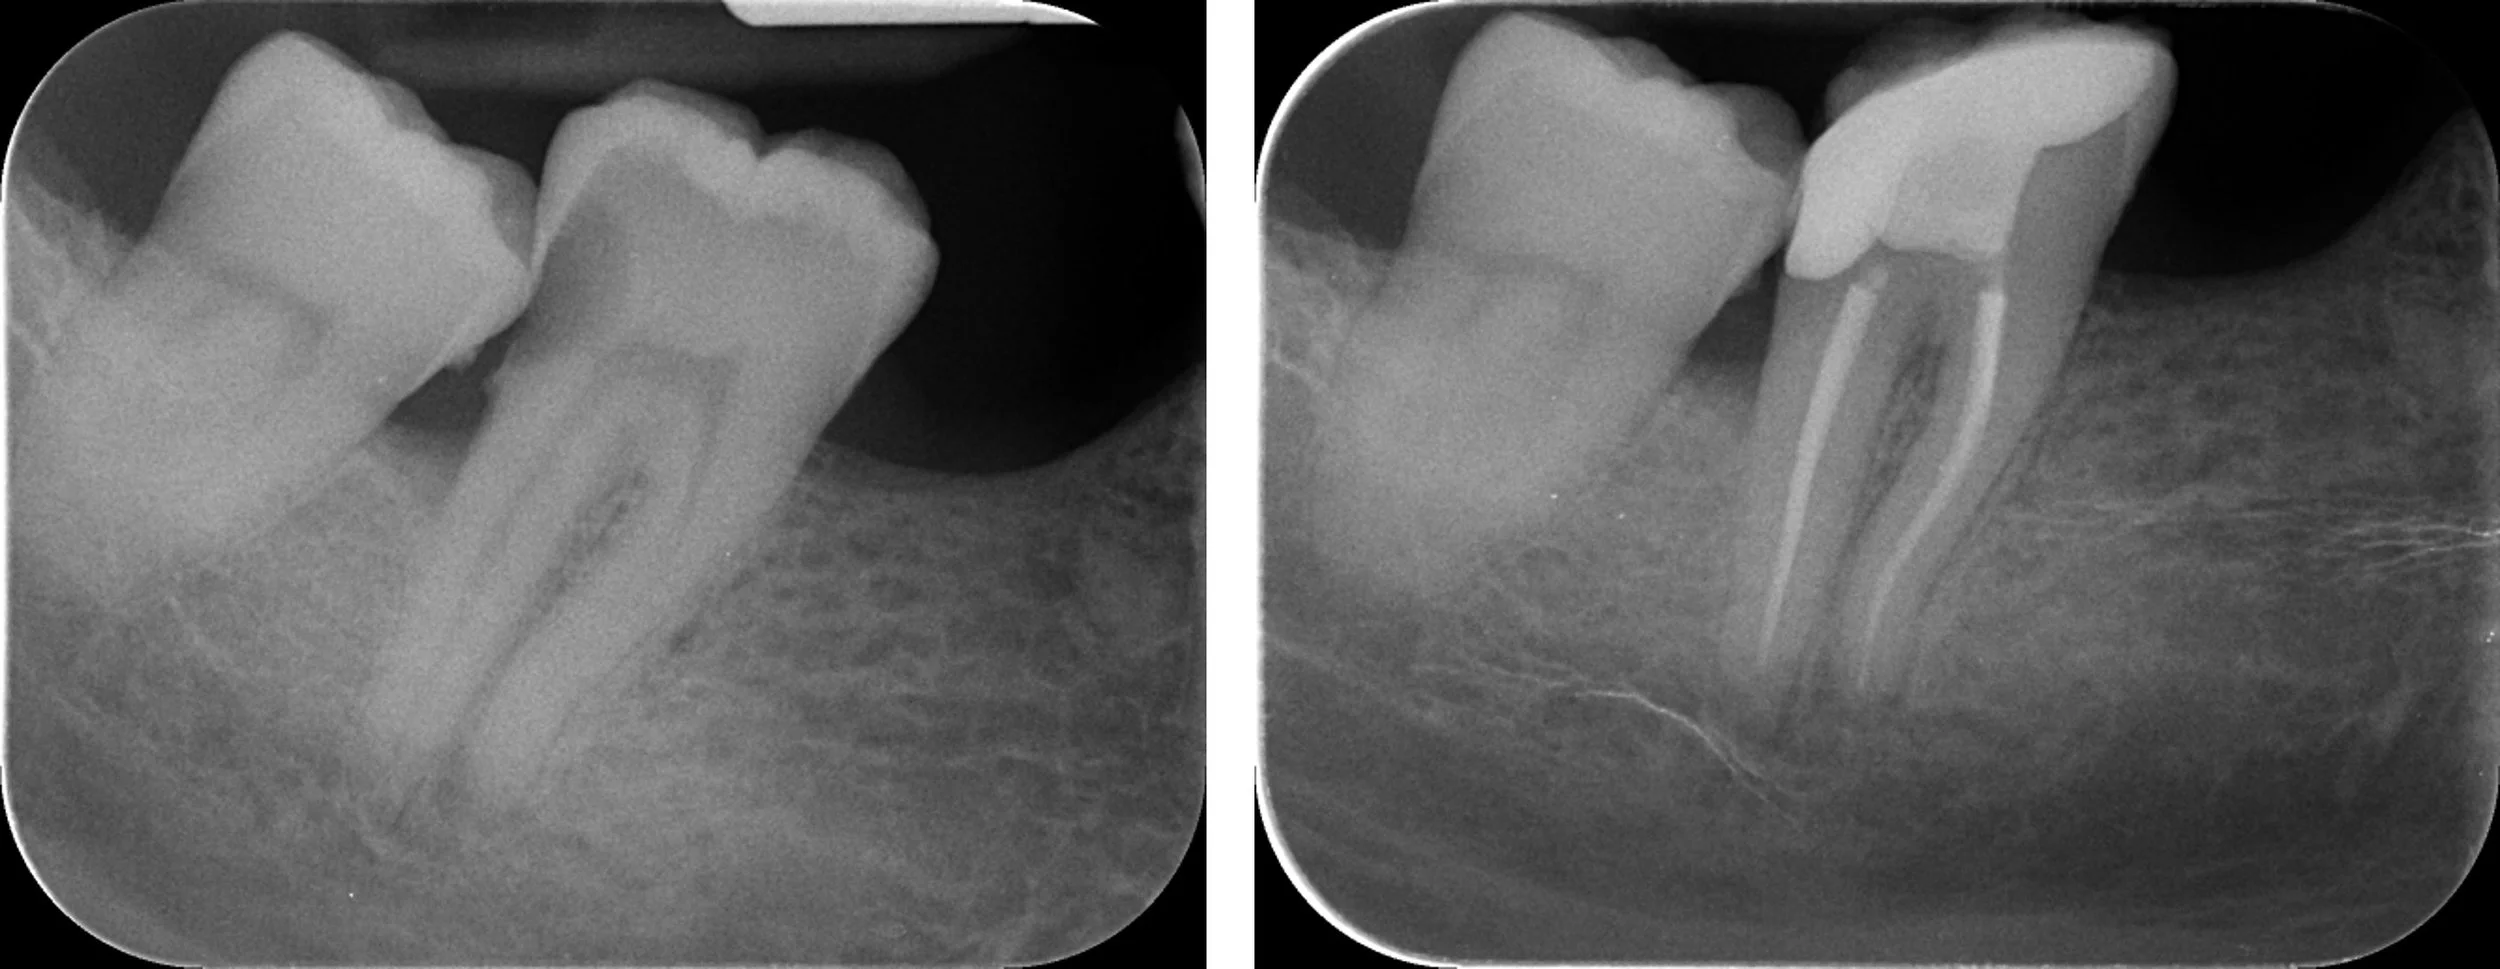

Precision root canal treatment under microscope.

All procedures completed under operating microscope — using the latest evidence-based techniques and premium materials for outcomes that last.